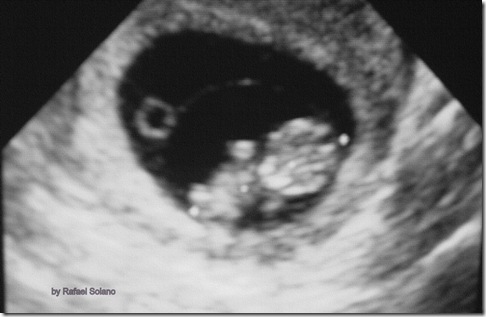

Aborto

Aborto es la terminación espontánea o intencional del embarazo ante de las 20 semanas. Más del 80% se produce durante las primeras 12 semanas de embarazo, y en más de la mitad de estos abortos tempranos la causa son anomalías cromosómicas.